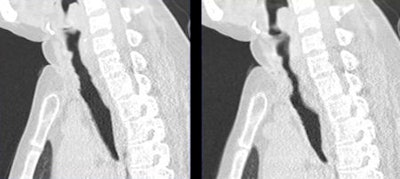

![]() |

| Patient with tracheomalacia. All images courtesy of Dr. Zhong-Xiang Ding. |